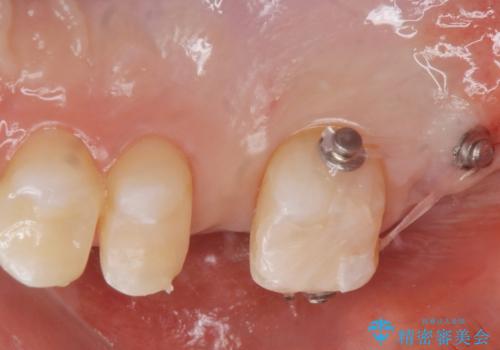

なので親知らずを抜歯して、一番奥の歯を部分矯正(upライト)をして倒れ込んでいる歯を起こしてスペースを作り、ブリッジの治療を行いました。

適合の良いブリッジが入りました。

歯の傾きを改善することにより食べ物が詰まりにくくなりました。